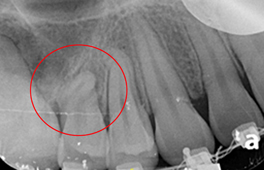

圖二、導航輔助齒瘤切除手術(來源提供:李慶璿醫師)

(左上)手術前,齒瘤纏繞鄰近牙齒的牙根。(左下)手術後,齒瘤完整摘除且鄰近的牙根完好無暇。(右)醫師手術中使用導航輔助摘除齒瘤手術。